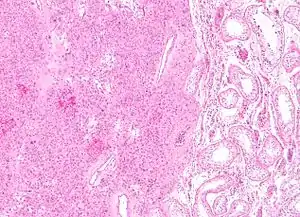

| Low magnification micrograph of a Leydig cell tumour. H&E stain. | |

Intermediate magnification micrograph of a Leydig cell tumour. H&E stain.

High magnification micrograph of a Leydig cell tumour. H&E stain.